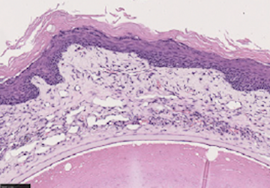

2019年に富山大学北島先生との共同研究によりAKCの病態によく似たモデルマウスを確立し、FADS(フェイズ)(Facial Atopic Dermatitis with Scratching)マウスと名付けました※5。このFADSマウスはアトピー性皮膚炎様の病態も発症することから、アトピー性皮膚炎の研究にも利用しているものです※6。このFADSマウスの眼病変にもペリオスチンが高発現していることから※7、ペリオスチンがAKCなどの原因となっているのではないかと考えました。

そこで、遺伝子改変技術により、生まれつきペリオスチン遺伝子を持っていないFADSマウスを作成したところ、眼病変(炎症や血管新生など)を発症しないか、眼病変が非常に軽度になりました。このことから、ペリオスチンがFADSマウスの眼病変の重要な原因となっていることが証明されました。